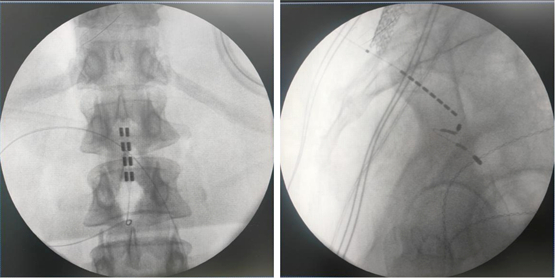

由于该患者为脊髓拴系,脊髓位置偏低,而且脊柱裂合并骶椎骨性解剖畸形给骶孔穿刺带来了非常大的难度,但是通过术前的系统评估以及术中电生理监测,李萃萃主任团队将一根穿刺电极精准置入S3骶孔位置以改善二便功能,另一根4-4排布的片状电极覆盖L1-2节段(患者脊髓低位,放置位置需根据患者情况个性化调整)以调控下肢肌张力异常和感觉障碍。术中测试显示,骶神经刺激可有效引发二便感知,脊髓电刺激则完整覆盖臀部及双下肢。